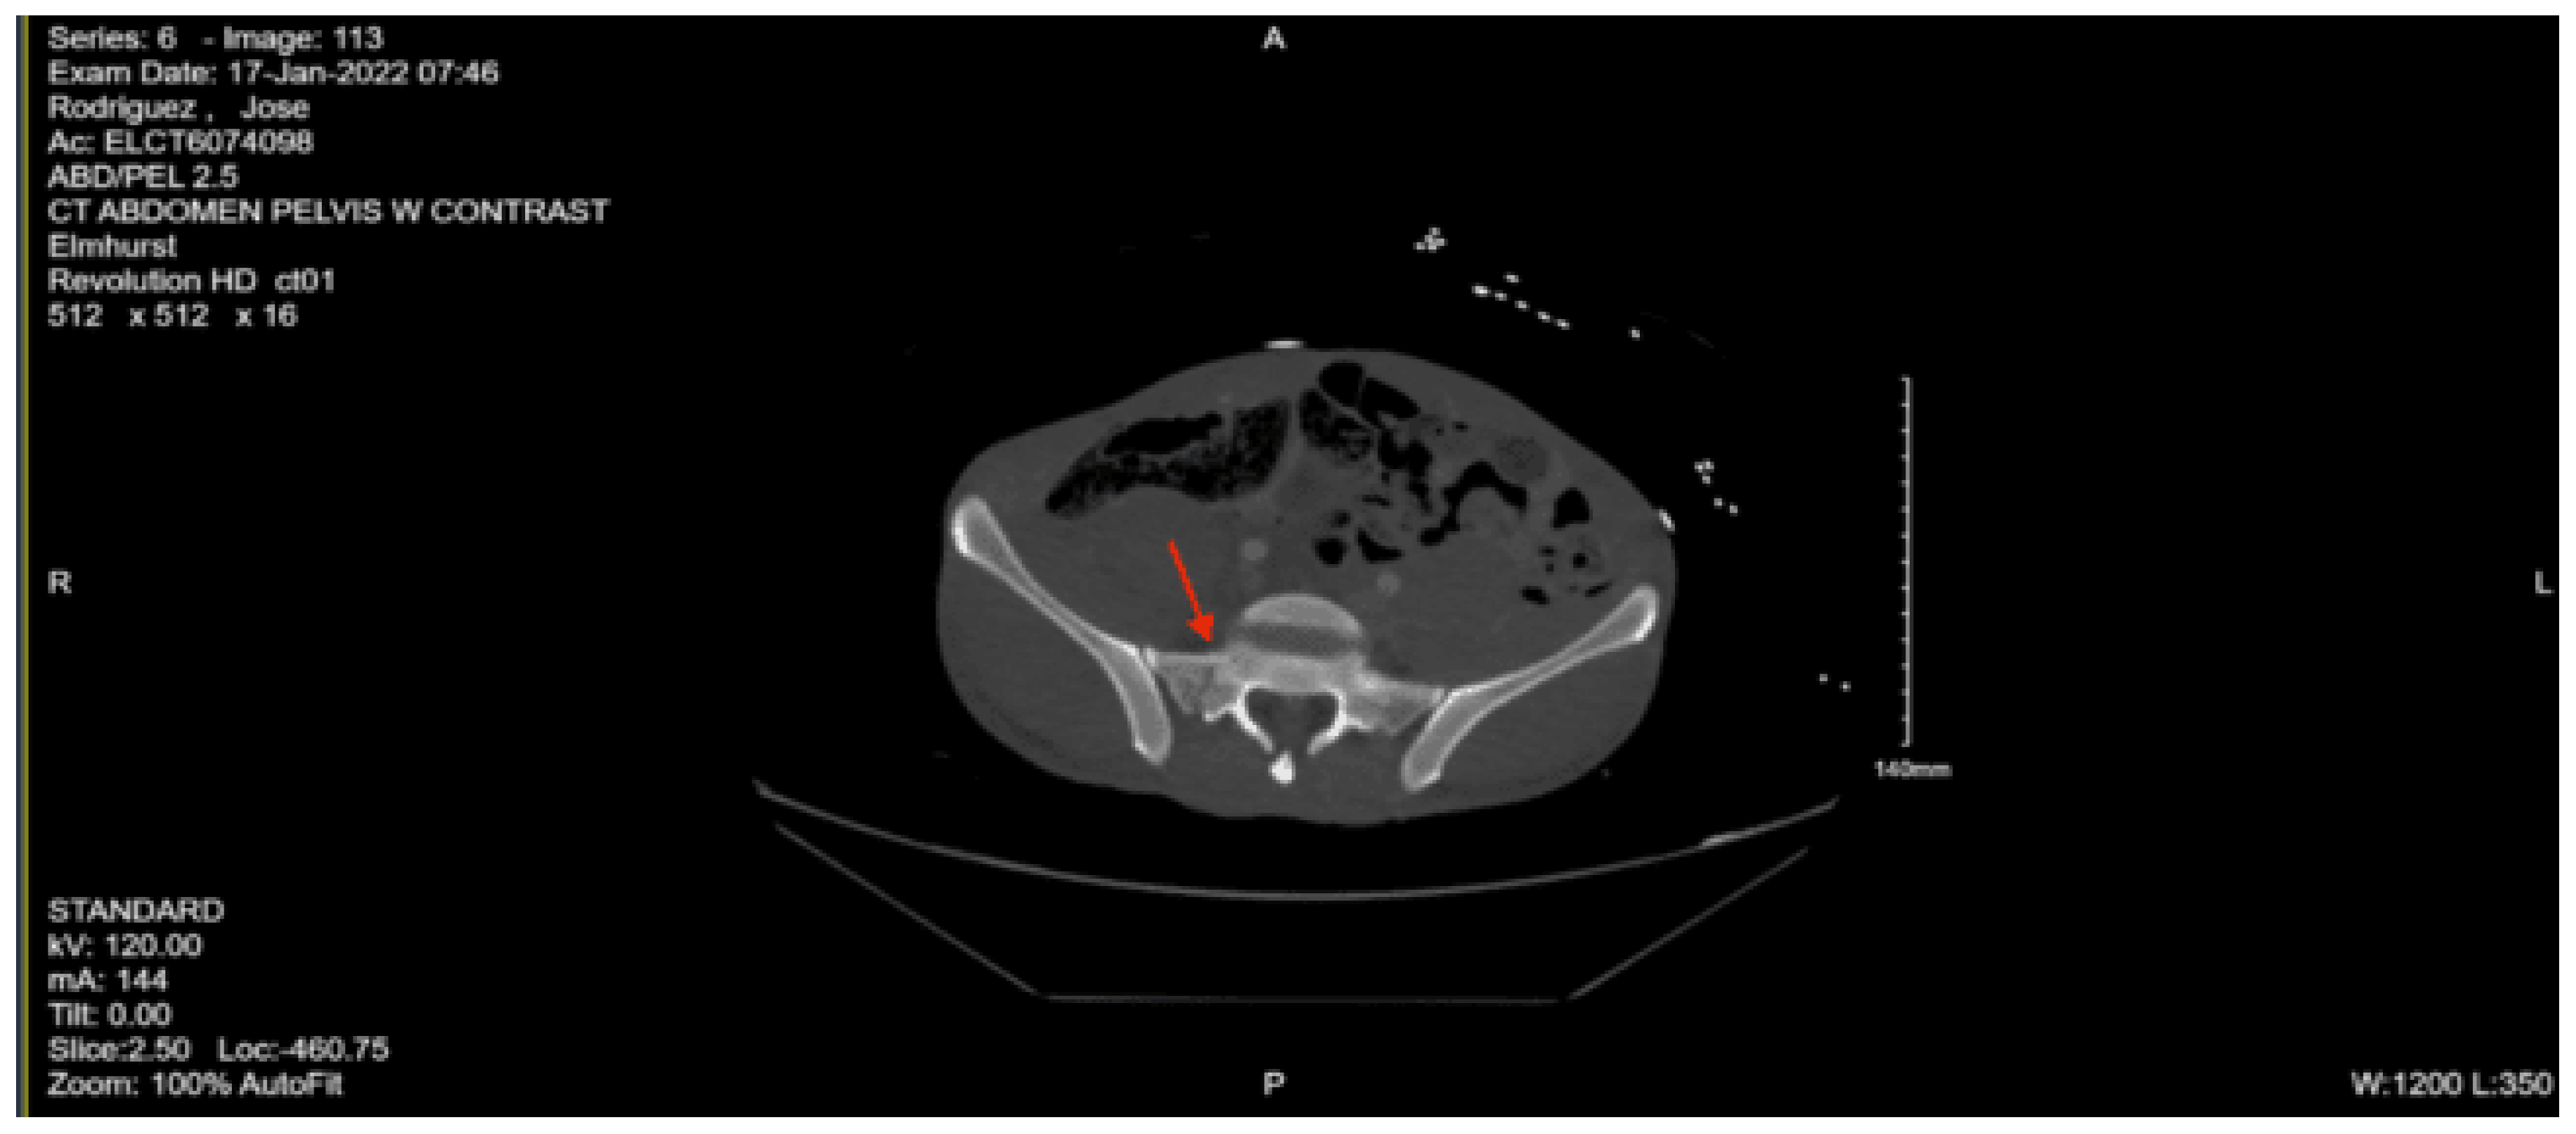

Imaging as shown in Figure 19 and Figure 20:

CT Abdomen Pelvic with contrast: No evidence of acute visceral injury. Redemonstration of fractures of the proximal right femur. Fractures of the right inferior petrous and right transverse processes of L2 and L3.

CT femur w/o contrast, Right: Comminuted fracture of the proximal subtrochanteric right femur with posterior medial displacement. Nondisplaced fracture of the right inferior pubic ramus.